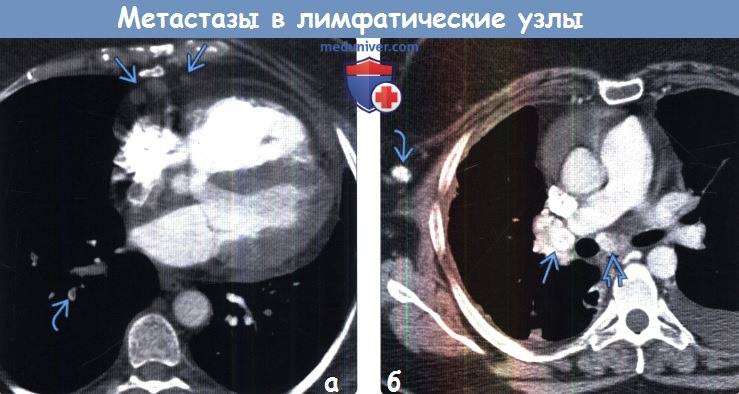

- КТ и МРТ — дают детальное изображение лимфоузлов и окружающих тканей

Показывает ли КТ метастазы в лимфоузлах? Да, опухолевые очаги могут быть видны на снимках. Но их не всегда удается отличить от неизмененной нормальной ткани. Всё же для достоверного подтверждения метастатического процесса в лимфоузлах золотым стандартом является ПЭТ-КТ.